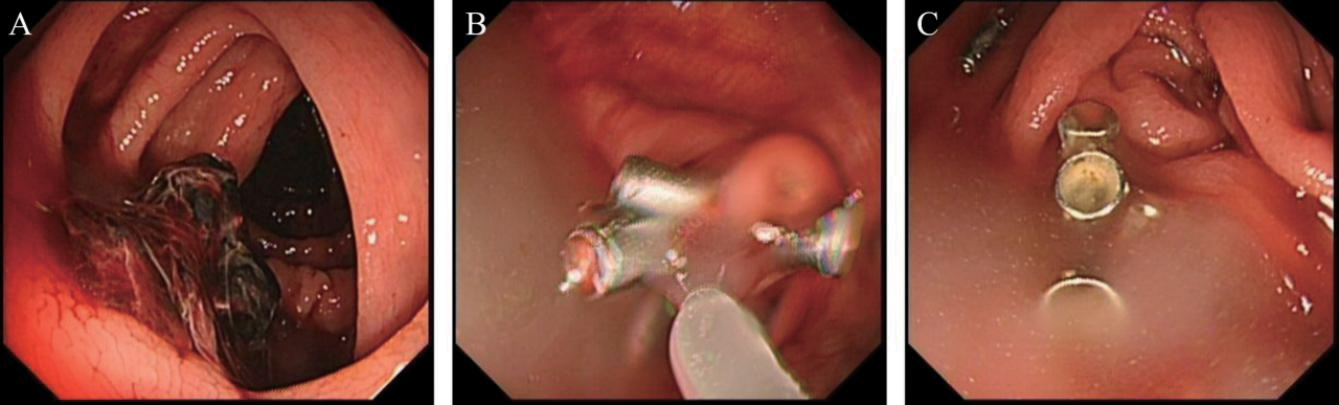

3.针对大肠ESD术后止血的应用

针对EMR较难完整切除的大肠肿瘤,选择ESD切除的技术日趋成熟,如何预防术中及术后出血仍然是重要问题。患者男,76岁,直肠肿瘤,ESD术后使用复合微孔多聚糖止血粉止血成功,见图3

图3 大肠ESD术后止血

A:行ESD术的直肠环肠腔二分之一大小约5.0 cm×6.0 cm侧向发育型肿物;B:ESD术后创面以复合微孔多聚糖止血粉外敷;C:术后无迟发性出血